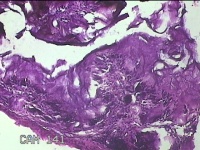

左肘关节肿物

左肘关节肿物(痛风石)

发现左肘关节肿物2年余。

灰白暗红色组织5.5x4x2.3cm一块,表面带梭形皮肤5.5x3.3cm,皮下见肿物5.5x2x1.3cm一个,切开肿物,内见大量石灰样物,内壁粗糙。